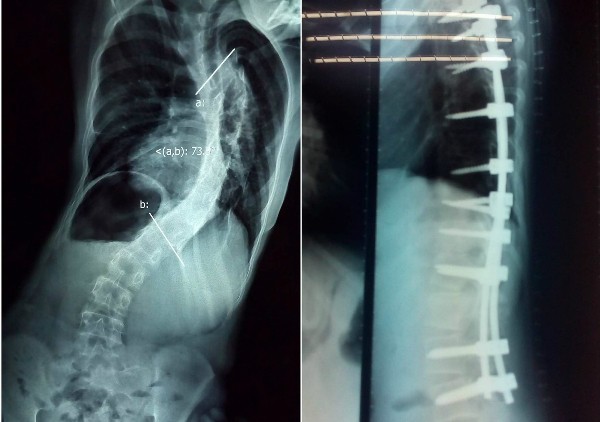

Cột sống bệnh nhi cong vẹo trước mổ (bên trái) và được nắn chỉnh sau mổ

Bé gái 12 tuổi đã bị vẹo lâu năm. Góc vẹo tại đoạn cong chính của cột sống lên đến 111 độ, kèm theo dị tật trong tủy sống cổ là bệnh rỗng tủy.

Suốt 2 tuần trước khi bé mổ, các bác sĩ sử dụng cách kéo liên tục qua vòng đầu Halo, tăng trọng lượng kéo dần để giảm độ cong cột sống. Bệnh nhi cũng được kiểm tra chức năng gan, thận, tim, phổi, tập vật lý trị liệu hô hấp, điều trị dinh dưỡng để có đủ sức khoẻ bước vào ca mổ.

Ngày 13/12, bác sĩ Vũ Viết Chính, Trưởng Đơn vị Cột sống Nhi và kíp mổ tiến hành phẫu thuật cho bệnh nhi. Các bác sĩ kết hợp sử dụng hệ thống theo dõi về thần kinh, tủy sống trong cuộc mổ. Đây là một phương tiện mới được áp dụng giúp kiểm soát tình hình và đảm bảo an toàn lúc phẫu thuật, giảm nguy cơ biến chứng liệt. Ca mổ thành công sau 5 giờ căng thẳng. Ba ngày sau mổ, bệnh nhi đi đứng được và xuất viện khỏe mạnh với dáng đi thẳng.